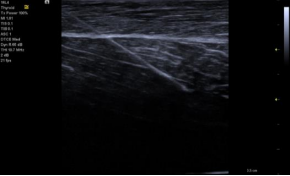

SieScape Panoramic Imaging(SieScape)宽景成像: 对于较大器官或病灶的观察,借助宽景成像,利用实时高分辨率灰度成像获得全景图像,方便观察靶目标的整体大小、形态以及毗邻位置,可在全景图像上进行测量、旋转等操作降低拼图测量产生的误差,且最长扫描长度>2 米,角度可达 180°,可应用与所有线阵及凸阵探头,应用领域广泛。